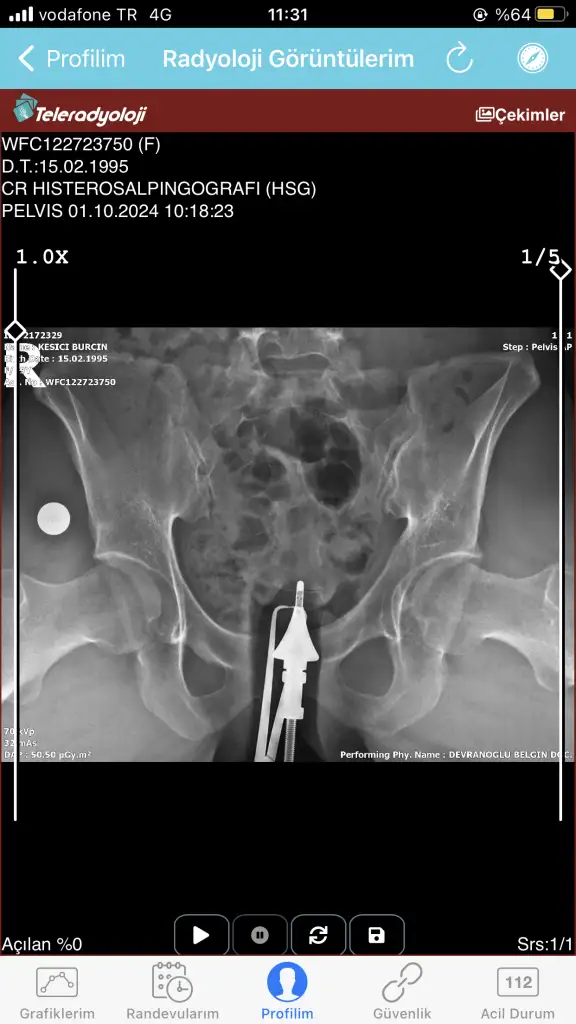

Bugün çekildim doktora gösteremedim daha anlayan yardımcı olabilir mi